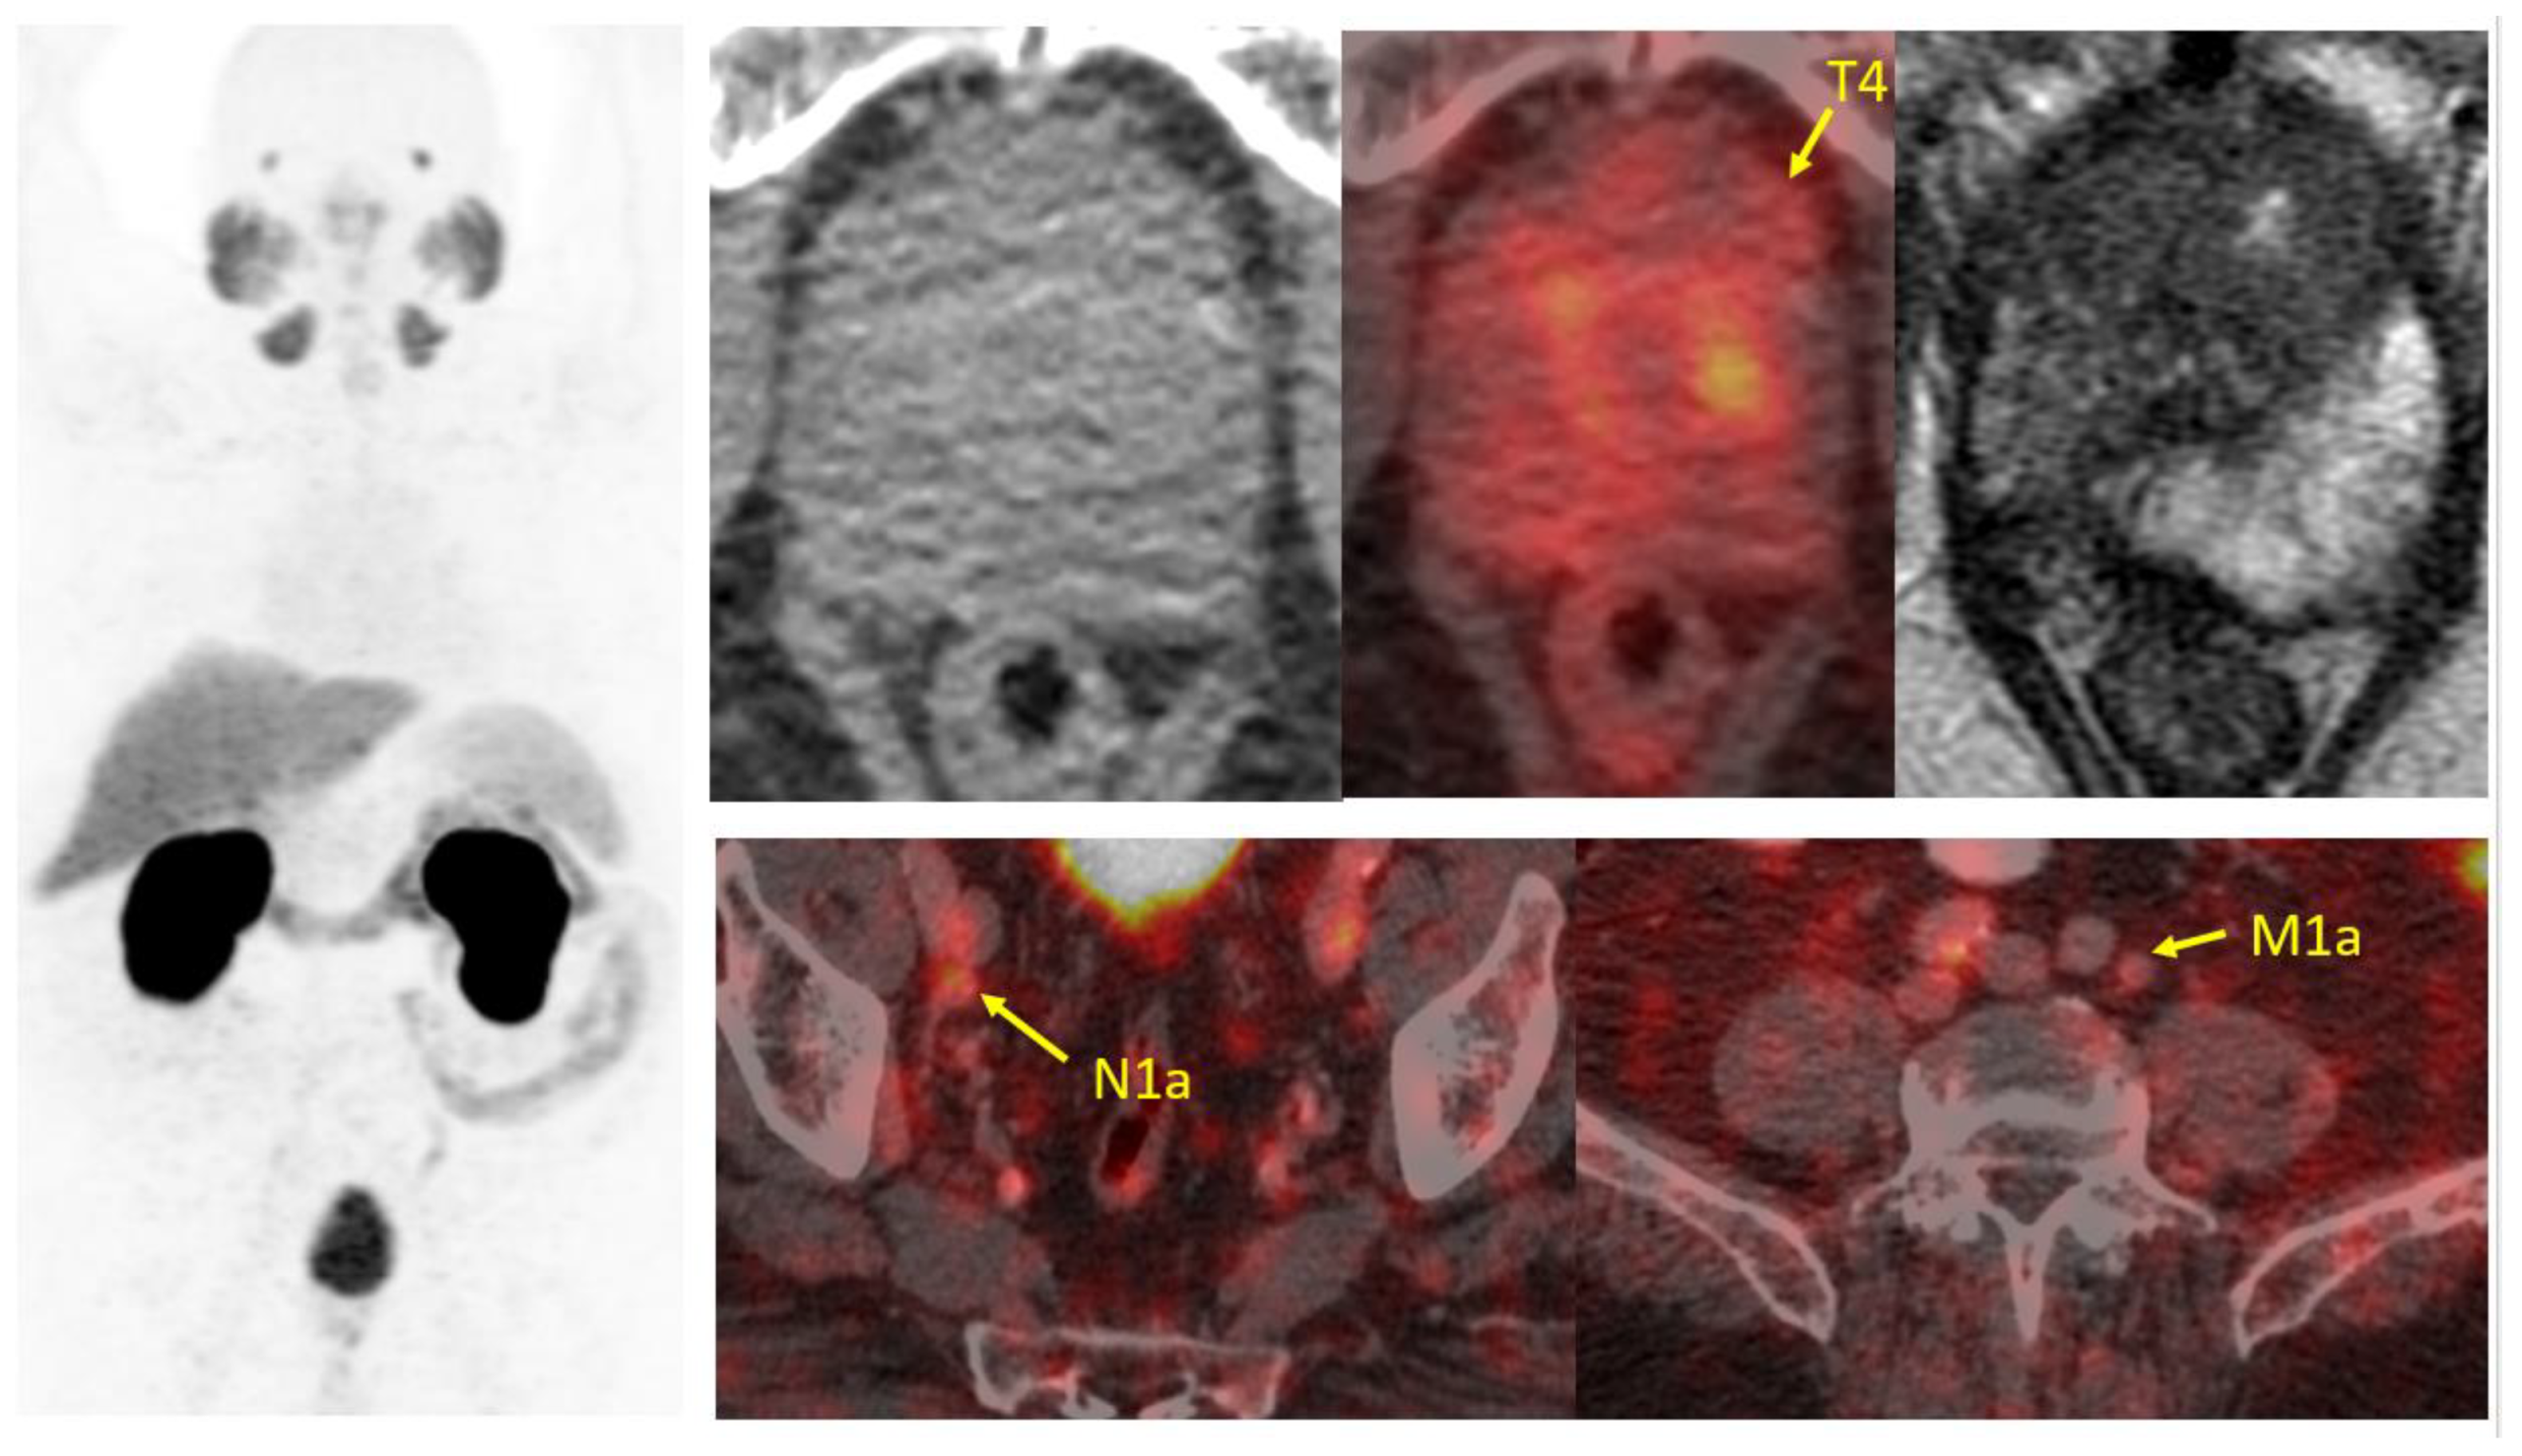

- Eiber, M.; Herrmann, K.; Calais, J.; Hadaschik, B.; Giesel, F.L.; Hartenbach, M.; Hope, T.; Reiter, R.; Maurer, T.; Weber, W.A.; et al. Prostate Cancer Molecular Imaging Standardized Evaluation (PROMISE): Proposed miTNMClassification for the Interpretation of PSMA-Ligand, P.E.T./.C.T. J. Nucl. Med. 2018, 59, 469–478. [Google Scholar] [CrossRef] [PubMed]